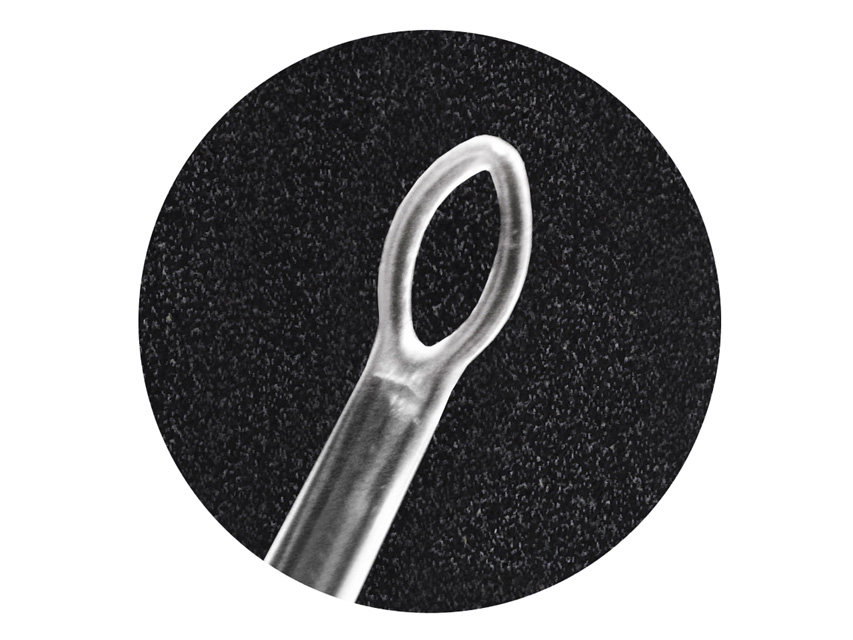

All’interno sono disponibili curettes auricolari, speculum auricolari e speculum nasali, strumenti essenziali utilizzati per l’esame e il trattamento delle vie uditive e nasali in contesti sanitari e professionali.

All’interno sono disponibili curettes auricolari, speculum auricolari e speculum nasali, strumenti essenziali utilizzati per l’esame e il trattamento delle vie uditive e nasali in contesti sanitari e professionali.